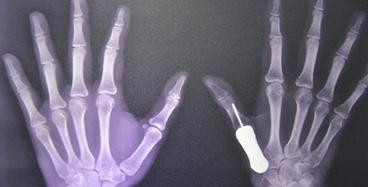

近日,全球首例3D打印鈦金屬假體(ti) 植入人體(ti) 手掌手術在泰國曼穀Phramongkutklao醫院獲得成功。